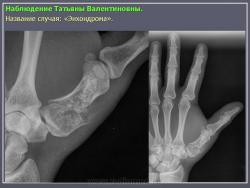

Энхондрома (син.: хондрома, центральная хондрома) — доброкачественная хрящевая опухоль, расположенная в костномозговом канале (интрамедуллярно). Встречается в 10 % случаев от общего числа доброкачественных опухолей костей. Считается, что она возникает из эктопически расположенных островков хряща, отщепившегося от пластинки роста на ранних этапах онтогенеза. В ряде случаев опухоль остается бессимптомной и обнаруживается случайно при рентгенологическом исследовании. В других случаях возникают боль и припухлость. Обычно болезненными становятся все энхондромы фаланг. Наиболее частая локализация: фаланги, главным образом, пальцев кистей, проксимальный конец плечевой кости, проксимальный или дистальный концы бедренной кости. При рентгенологическом исследовании в энхондроме определяются просветления с участками минерализации. Тень кости становится более широкой, кортикальный слой сохраняет целостность, но истончается. В редких случаях энхондрома имеет вид эксцентрически растущего экзофитного новообразования. Макроскопически опухоль представляет собой голубовато-белую полупрозрачную хрящевую ткань, в которую вкраплены желтоватые участки обызвествления. Опухоль состоит из отдельных хрящевых узелков, диаметр которых варьирует в пределах 1 см.

Рентгенологическая картина хондромы представляет четко очерченный опухолевый узел. Очаги минерализации в хондромах выглядят достаточно характерно и представлены очаговыми, глыбчатыми или кольцевидными , арочными отложениями извести. Полного разрушения кортикального слоя трубчатой кости с выходом опухолевых масс в мягкие ткани не наблюдается.